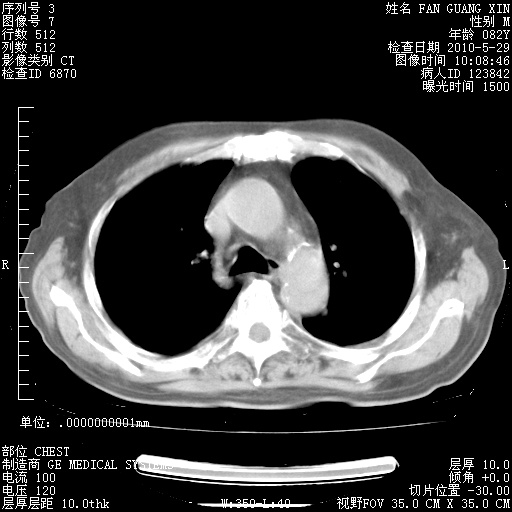

治疗3周后的肺部CT纵隔窗

从胸部影像学来看,的确有好转。至于目前为何发热不甚清楚?除了发热还有其他症状如有无喀痰,痰呈丝状吗?等等。尽量搜寻有无致发热其它可能原因?真菌?其它?如果的确无其他致发热的原因,考虑将甲强龙调至60-80mg bid/日。免疫全套基本无异常,考虑多系特发性肺间质纤维化